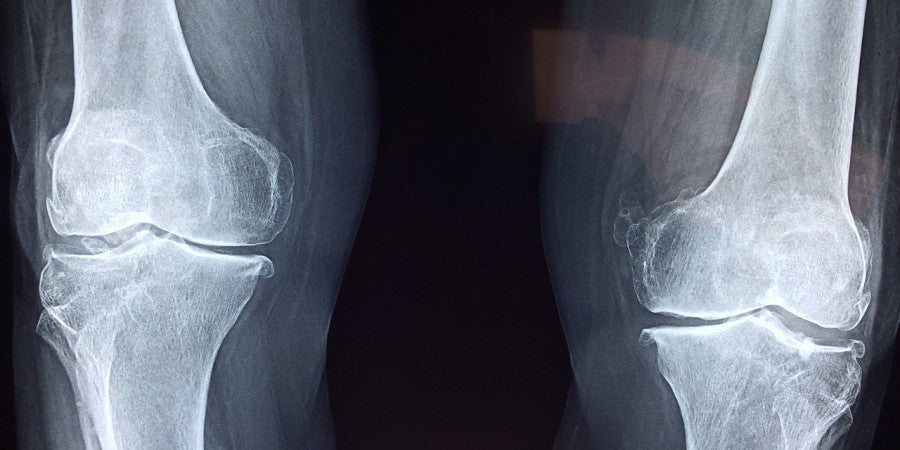

WU: Das ist richtig. Die Beinstrecker- oder auch Legextension-Maschine, empfehle ich ausschliesslich in speziellen Ausnahmefällen. Sie bringt mehrere Nachteile wie eine geringe Überladung der exzentrischen Kontraktion, ein neurologisch im Alltag und sport irrelevantes Bewegungsmuster und eben den Schubladeneffekt mit sich. Der Schubladeneffekt ist ein vor oder zurück gleiten des Unterschenkels im Knie. In der Physiotherapie wird dieses Vor- und Zurückgleiten im Gelenk durch den Schubladentest (engl. Drawertest) bei einem Kniewinkel von 90° zur Diagnostik der Kniestabilität verwendet. Dieses Zurückgleiten entsteht ebenfalls in der obersten (kontrahierten) Position bei der Beinstrecker-Maschine. Durch den horizontalen Druck auf den Unterschenkel kann dieser im Gelenk minimal nach hinten gleiten. Dies verursacht bei vielen Trainierenden mittelfristig Probleme wie vor allem eine Entzündung der Patellasehne. Grundsätzlich ist der natürliche Druck auf den Unterschenkel in > 99% aller Bewegungsmuster vertikal. Wenige Ausnahme wie der Schuss beim Fussball oder ein Tritt im Kampfsport kombinieren vertikale Kräfte (das Ausholen) mit horizontalen Kräften (Kontakt mit Ball oder Gegner). Jedoch sind auch in diesen Fällen in Volumen und Widerstand die vertikalen Kräfte die primären Kräfte. In über 99% aller Bewegungsmuster des Alltags und Sports sind die Kräfte jedoch nicht horizontal sondern vertikal. Das sind grundsätzlich alle Bewegungsmuster bei denen wir auf beiden oder einem Bein stehen oder aufkommen. Das Kniegelenk ist mechanisch nicht dafür ausgelegt in höherem Volumen horizontale Kräfte auf den Unterschenkel und damit den Schubladeneffekt zu tolerieren. Der Beinstrecker kann in fortgeschrittenem Training mit Bodybuilding-Zielen am Ende eines Training im vorermüdeten Zustand ein gutes Tool sein um den Quadrizeps noch mehr Wiederholungen und metabolen Stress auszusetzen sowie das letzte bisschen Glykogen zu verbrauchen. Im Trainingsalltag von > 99% der Trainierenden findet er jedoch keinen Platz wenn das Ziel progressives Training ist – durch eine geringe Überladung der exzentrischen Kontraktion, ein neurologisch im Alltag und für Sportarten irrelevantes Bewegungsmuster und eben den Schubladeneffekt.

Bild: Die Kniegelenke.